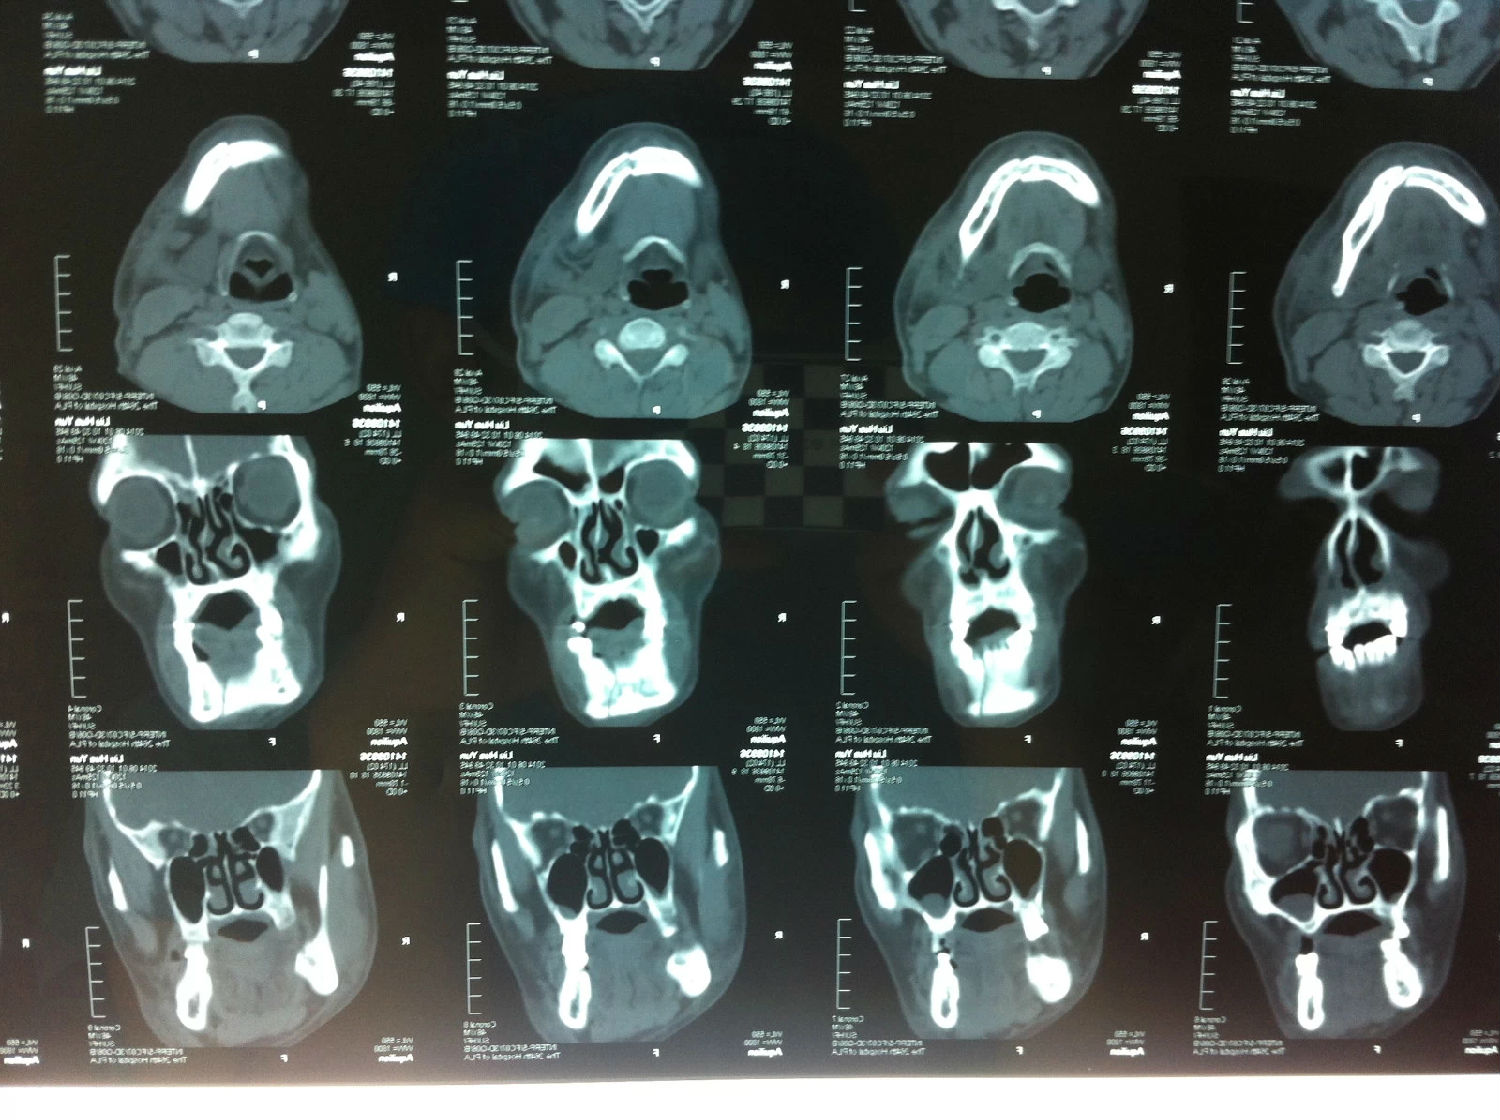

入院后全麻下手術(shù)治療,左側(cè)下頜骨囊腫較大,術(shù)前考慮病理性骨折可能,準(zhǔn)備鈦釘鈦板固定,術(shù)中摘除囊腫后,發(fā)現(xiàn)下頜骨下緣骨量尚可,未給予固定。術(shù)后病理診斷為下頜骨角化囊腫,考慮到患者可能為基底細(xì)胞癌綜合征,術(shù)中切除頸部皮膚痣兩處,術(shù)后病理診斷為:皮膚痣,排除基底細(xì)胞癌綜合征?;颊哂凶髠?cè)第六肋骨分叉肋,綜合以上特征,最終診斷為多發(fā)性頜骨囊腫綜合征。